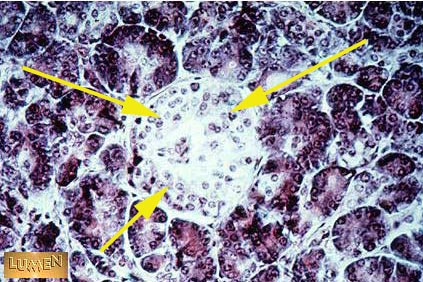

What do these cells secrete?

Answer

Insulin,

glucagon,

and somatostatin.